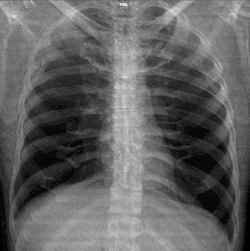

A chest X-ray showing a very prominent wedge-shape area of airspace consolidation in the right lung characteristic of acute bacterial lobar pneumonia.